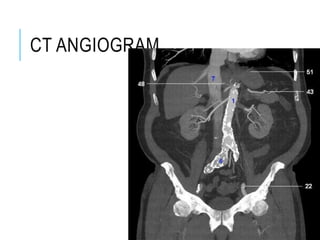

CT ANGIOGRAM

DIGITAL SUBTRACTION

ANGIOGRAPHY

VOLUME

RENDER

ED

SURFAC

E

SHADED

CT

ANGIOG

RAM OF

THE

MAJOR

BRANCH

ES OF